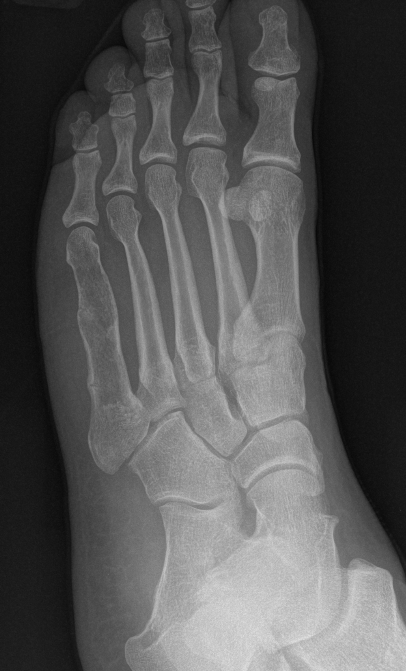

X-ray

Intralesional calcification - punctate, stippled calcification and broken rings

Hand / Foot

Foot